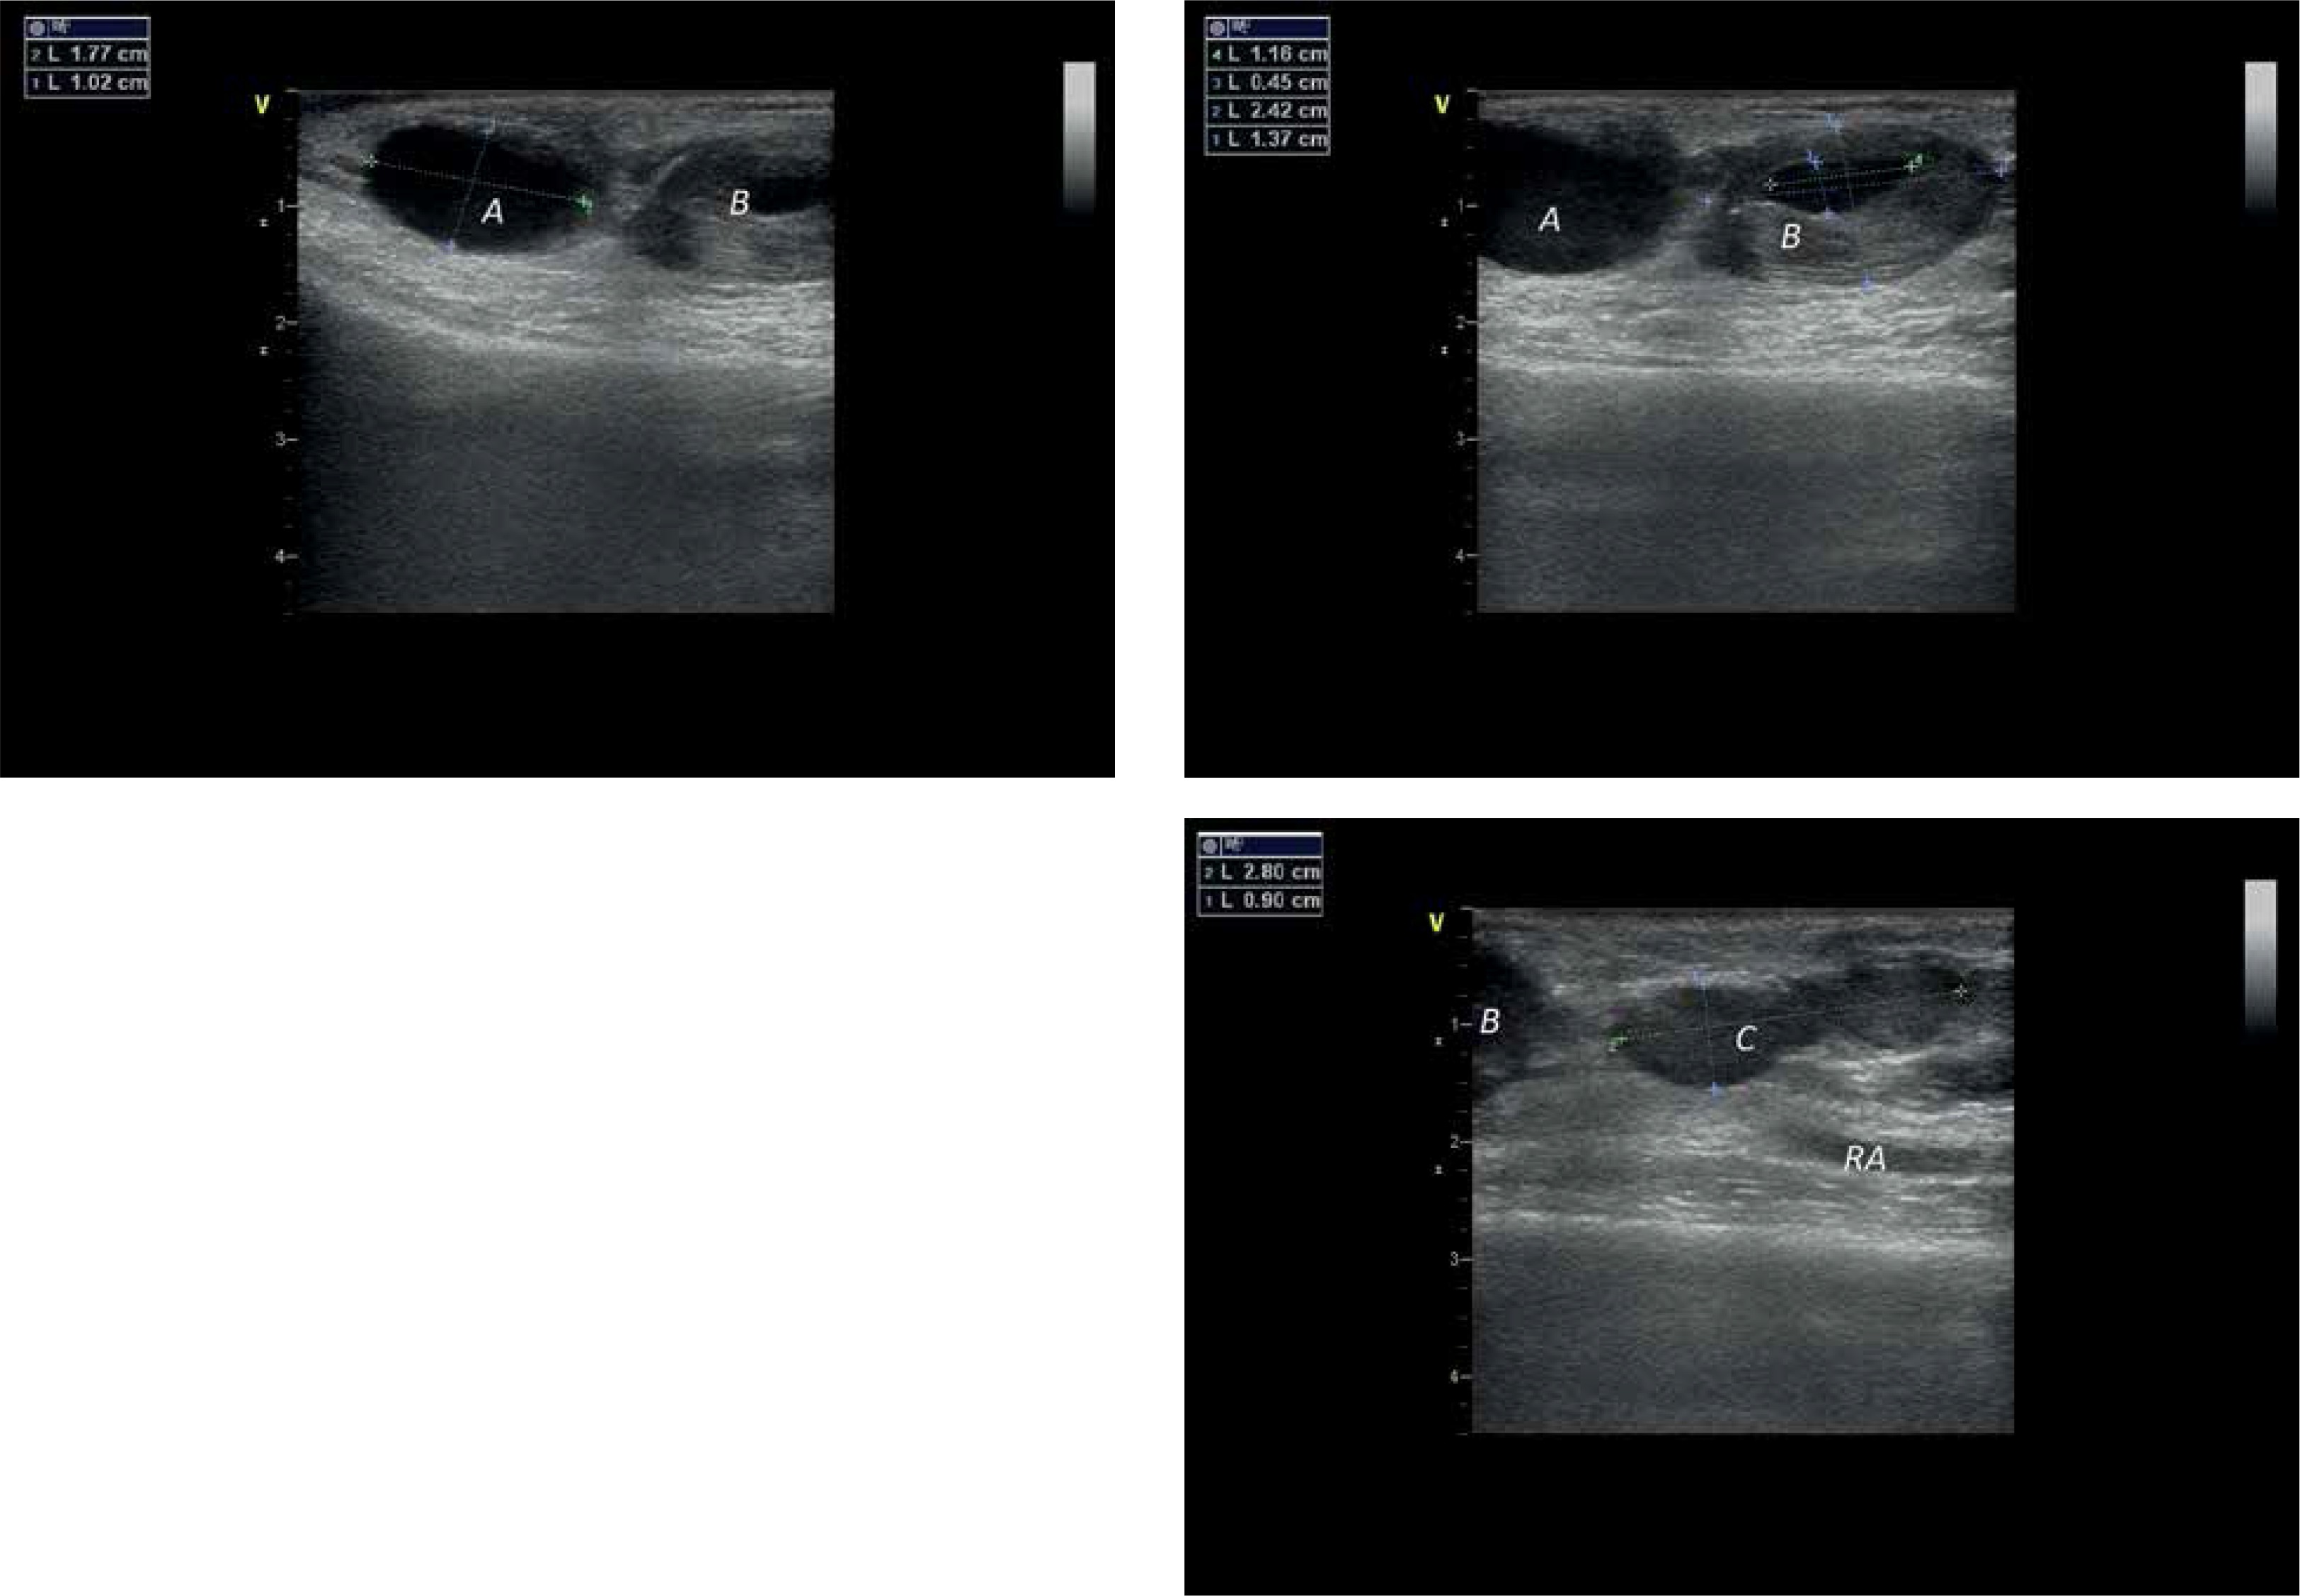

Figure 4

Communication between the first and second chamber with a flow characteristics

A – first chamber, B – second chamber.

Figure 5

Effect of thrombin injection resulting in complete flow stop by clot filling first of the chambers

A – first chamber, B – second chamber, RA – radial artery.